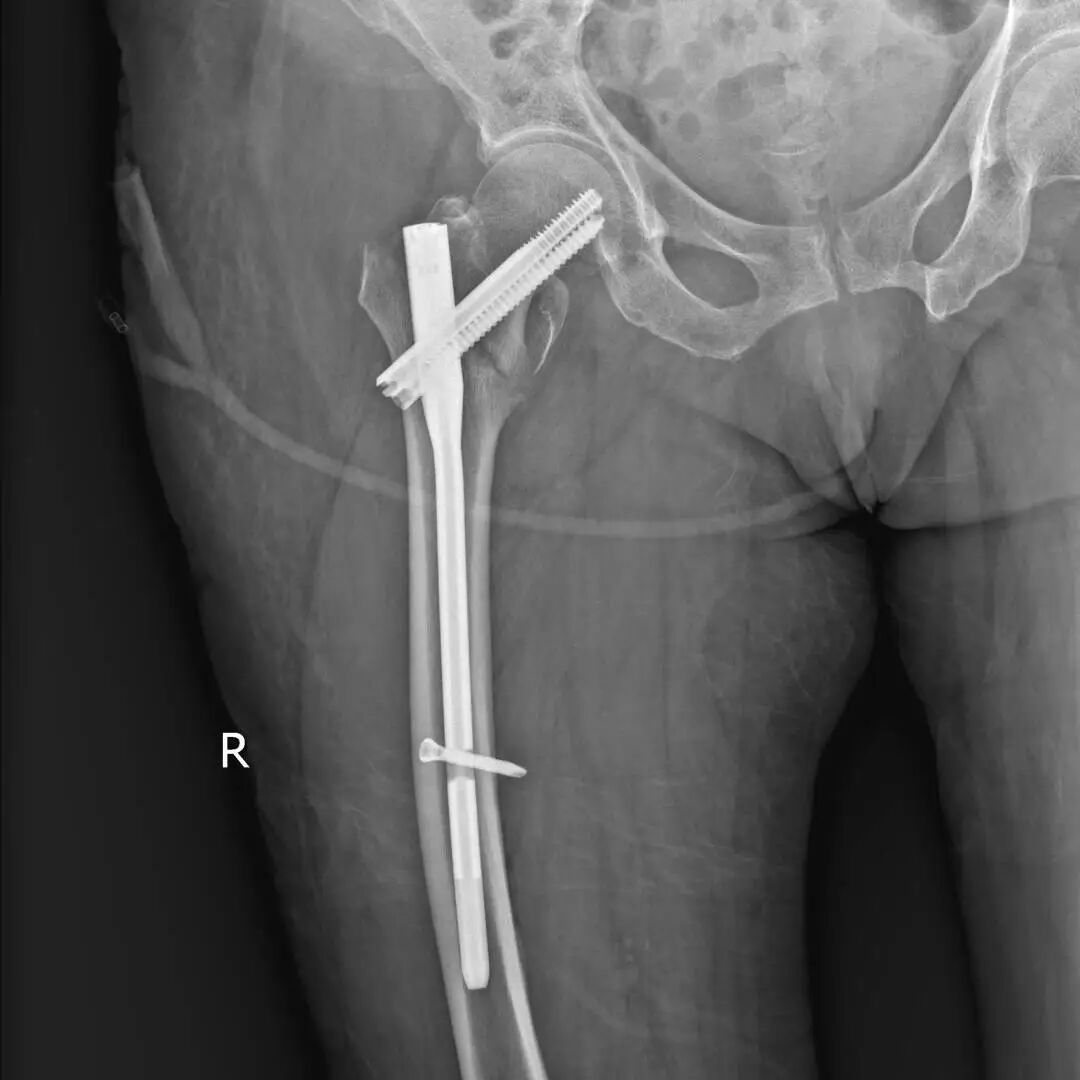

莊奶奶右股骨粗隆区粉碎性骨折,合并窦性心动过缓(已安装心脏起搏器)及高血压2级,手术风险极高。

孙大川主任团队联合麻醉科、心内科多学科会诊,在全麻下开展“闭合复位内固定术”。

术中通过微创技术精准复位骨折端,植入钛合金髓内钉系统。手术全程仅1小时,出血量少。

术后X光片